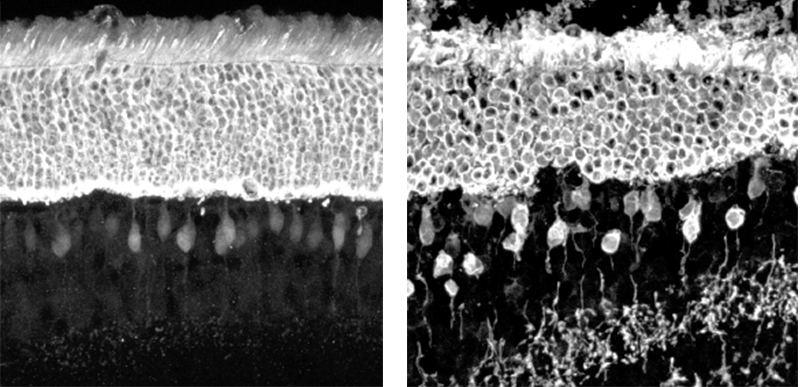

Researchers affiliated with the Lowy Medical Research Institute have made important, and surprising, discoveries about photoreceptors in the MacTel eye. While it was once thought that the photoreceptors in the “MacTel zone” died, there is new evidence that this is not necessarily the case. Photoreceptor cell bodies remain intact, and, furthermore, some cells in the MacTel lesion retain the ability to detect light. These discoveries were made through the use of an advanced imaging technique called adaptive optics, in the laboratories of Austin Roorda and Joseph Carroll.